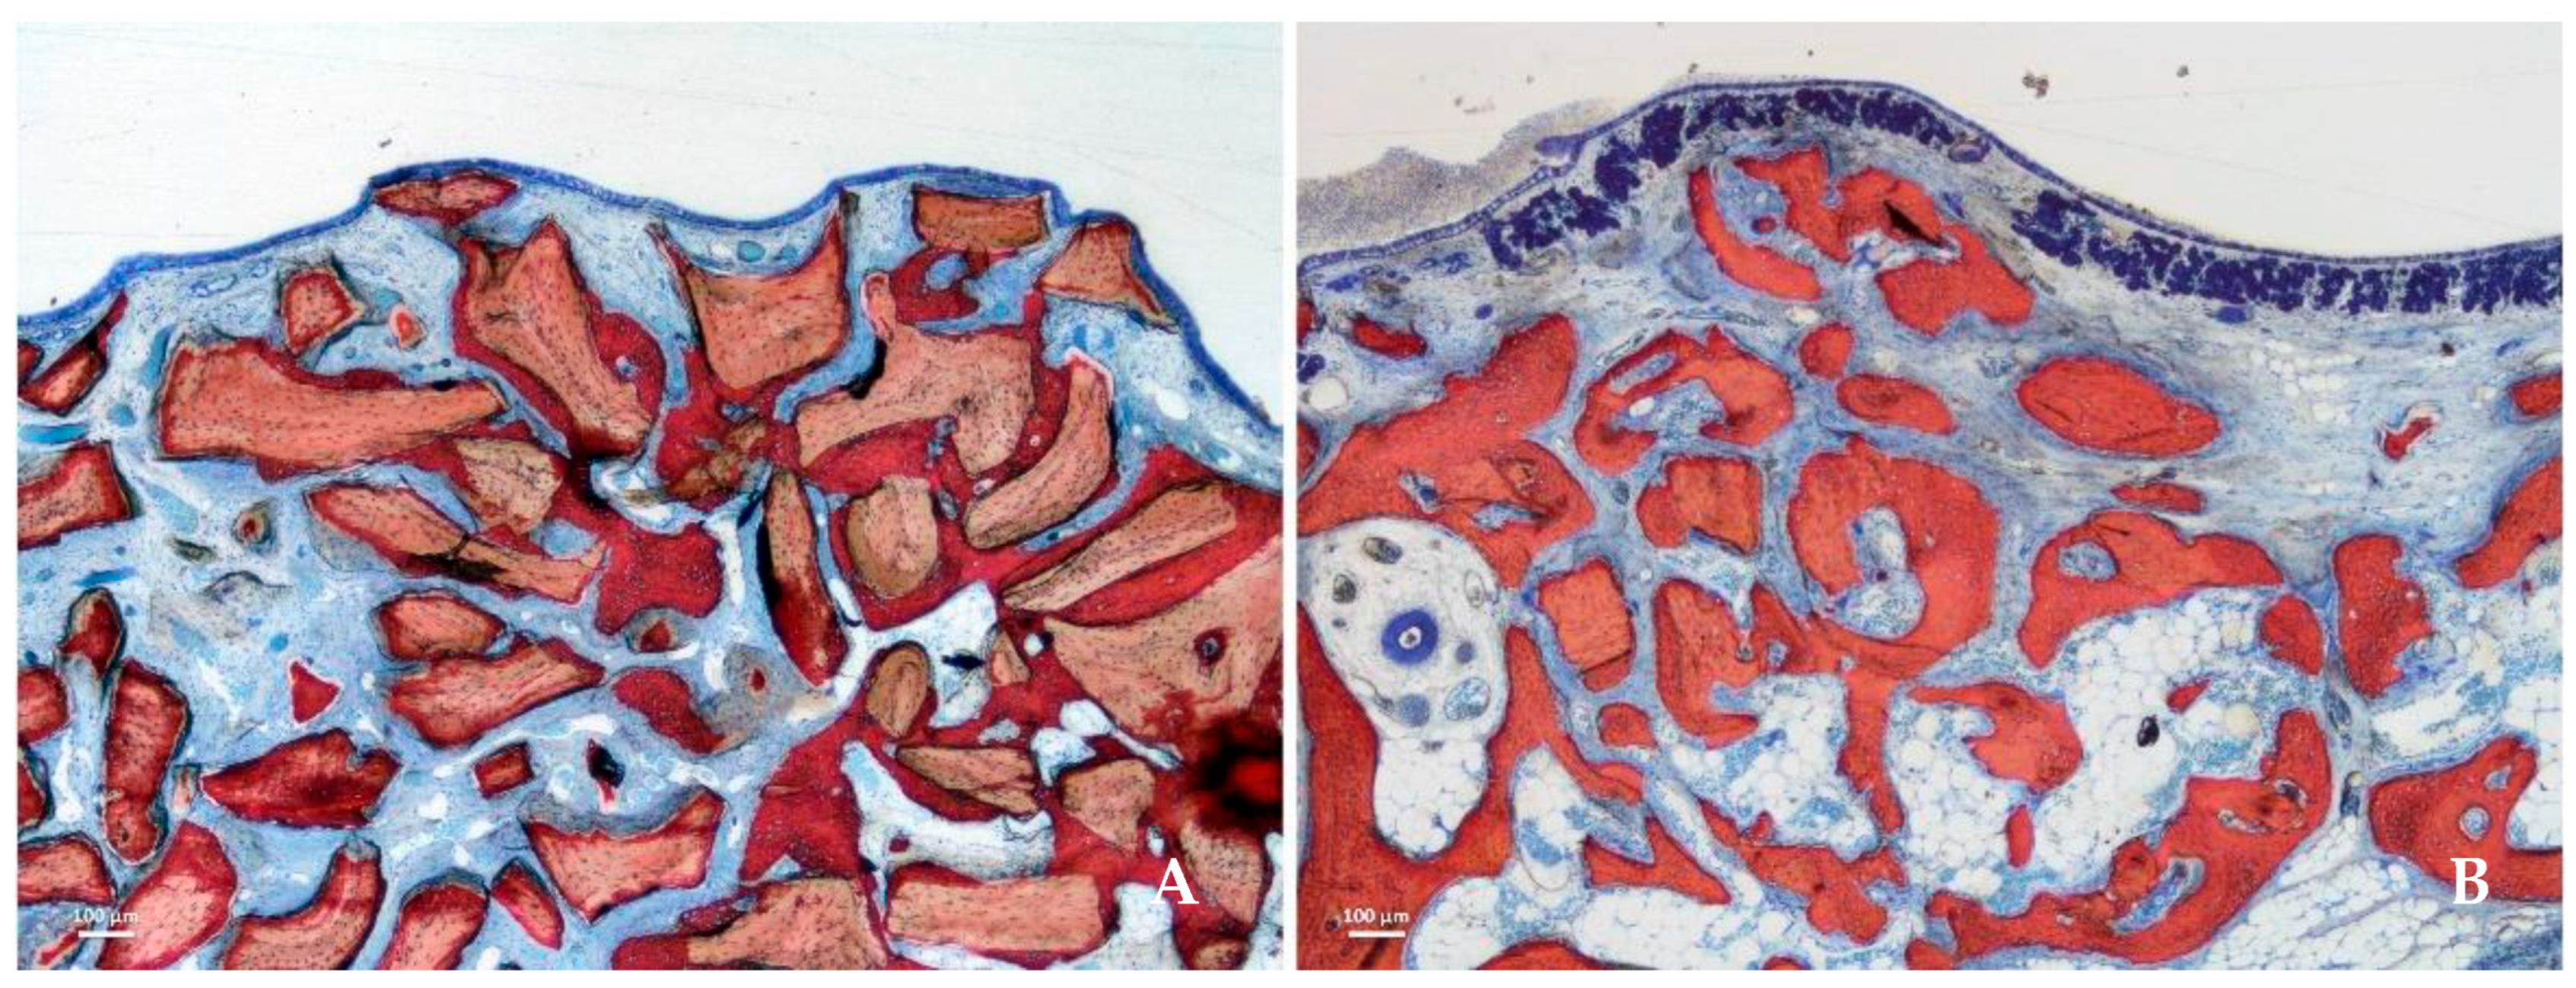

| Collagenated porcine bone (mp3®) |

Evaluate materials with preserved natural collagen for better clot stability and cell migration.

Synchrotron radiation X-ray microtomography; histological evaluation; 3D quantitative trabecular analysis over time. | Gradual graft resorption; excellent trabecular organization; improved early integration and cellular infiltration. | [46] |